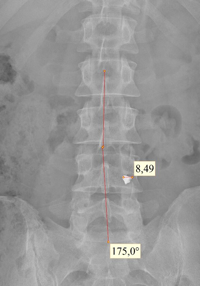

При поступлении пациента в наш госпиталь ему были выполнены рентгенография и КТ исследования пояснично-крестцового отделов позвоночника. Обнаружено инородное тело (осколок) в межпозвонковом отверстии LIV-LV слева.

Рис. 1 Рентгенография поясничного отдела позвоночника в прямой проекции. Визуализируется металлический осколок в межпозвонковом отверстии на уровне LIV-LV позвонков слева.